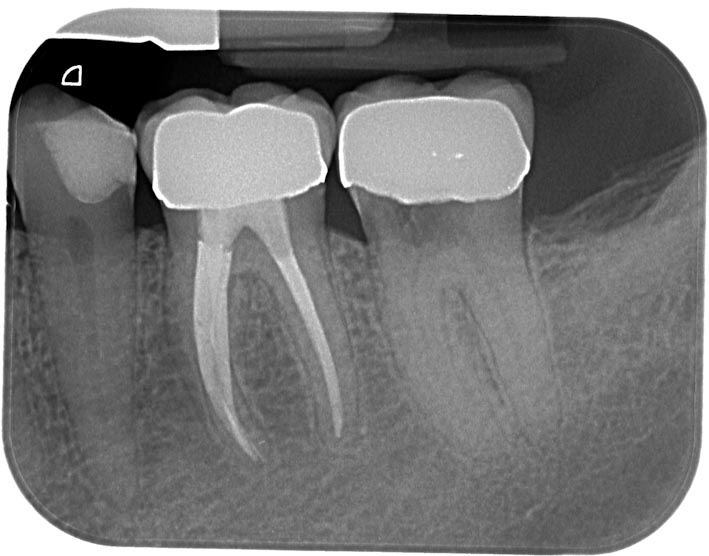

IR20100825-1 Veröffentlicht 1. Juli 2013 am 709 × 556 in Was zeigt das DVT ? (4) – Resorptionen- Die Antworten Teil 3 : Fall 2 Kontrolle August 2010